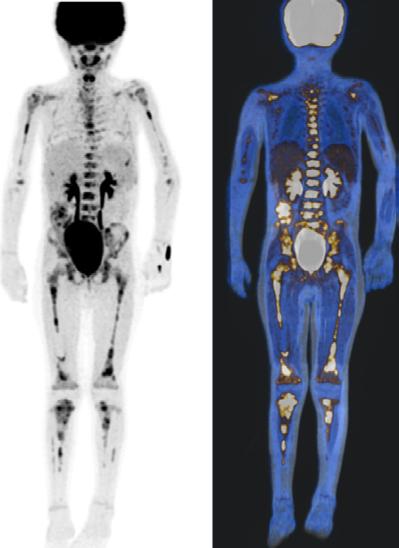

Figura 1A) Estudio PET con 6-[18F]FDOPA positivo para actividad tumoral del primario conocido en abdomen y retroperitoneo, con metástasis difusas en la médula ósea del esqueleto axial y apendicular.

Figura 1B) Estudio PET con [18F]OCTREOTIDE con sobreexpresión anormal de los receptores de somatostatina en retroperitoneo y esqueleto axial y apendicular.

Al correlacionar con 6-[18F]DOPA (Figura 1A) se observa que las lesiones tienen mayor sobreexpresión de los receptores de somatostatina.

Femenino de 7 años con diagnóstico de Neuroblastoma, se realiza PET/RM con [18F]F-DOPA para estadiaje, con evidencia de lesión primaria a nivel de retroperitoneo y conglomerados locoregionales así como infiltración a médula ósea del esqueleto axial y apendicular (Figura 1A), posteriormente la paciente fue tratada quirúrgicamente con resección de la lesión primaria así como tratamiento con inmunoterapia y transplante autólogo de médula ósea además de radioterapia. Al presentar refractariedad al tratamiento comentado, se plantea la posibilidad de administrar Lutecio (177Lu) oxodotreotide, por lo que se sugiere realizar PET/RM con [18F]Octreotide para valorar expresión de receptores de somatostatina y considerar la terapia con radionúclidos para receptores de péptidos (PRRT), el estudio muestra evidencia de sobreexpresión anormal de dichos receptores en retroperitoneo, espacio subpleural izquierdo además de esqueleto axial y apendicular (Figura 1B).